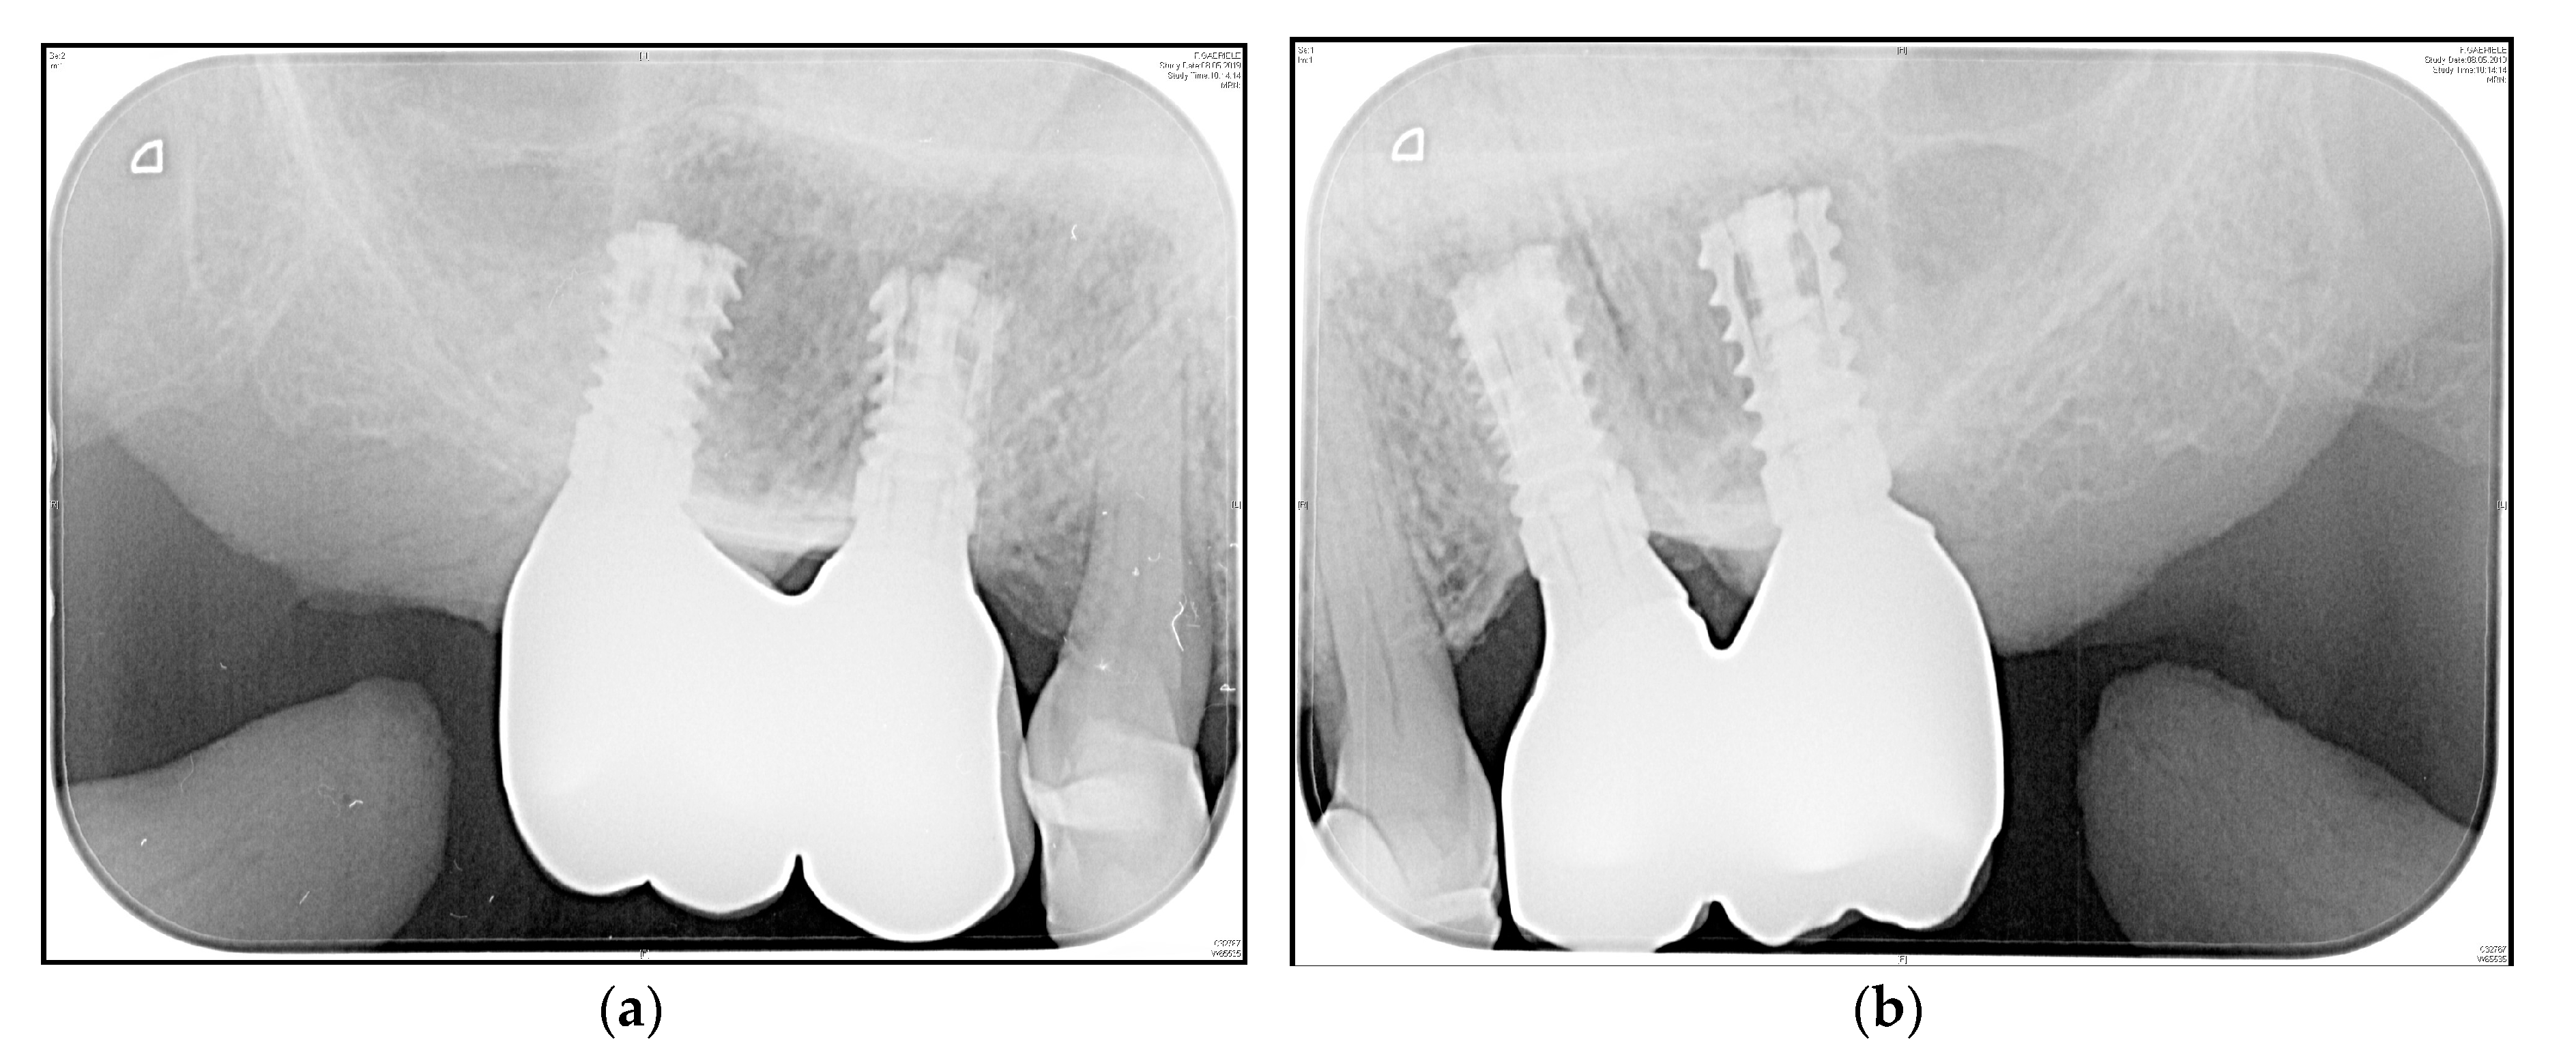

3.4. Crestal Bone Changes

4. Discussion

4.3. Peri-Implant Crestal Bone Loss